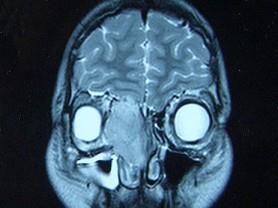

女,16岁,鼻塞、流涕一年余,失去嗅觉,影像检查如图所示,最可能的诊断是 ( )

答案: E